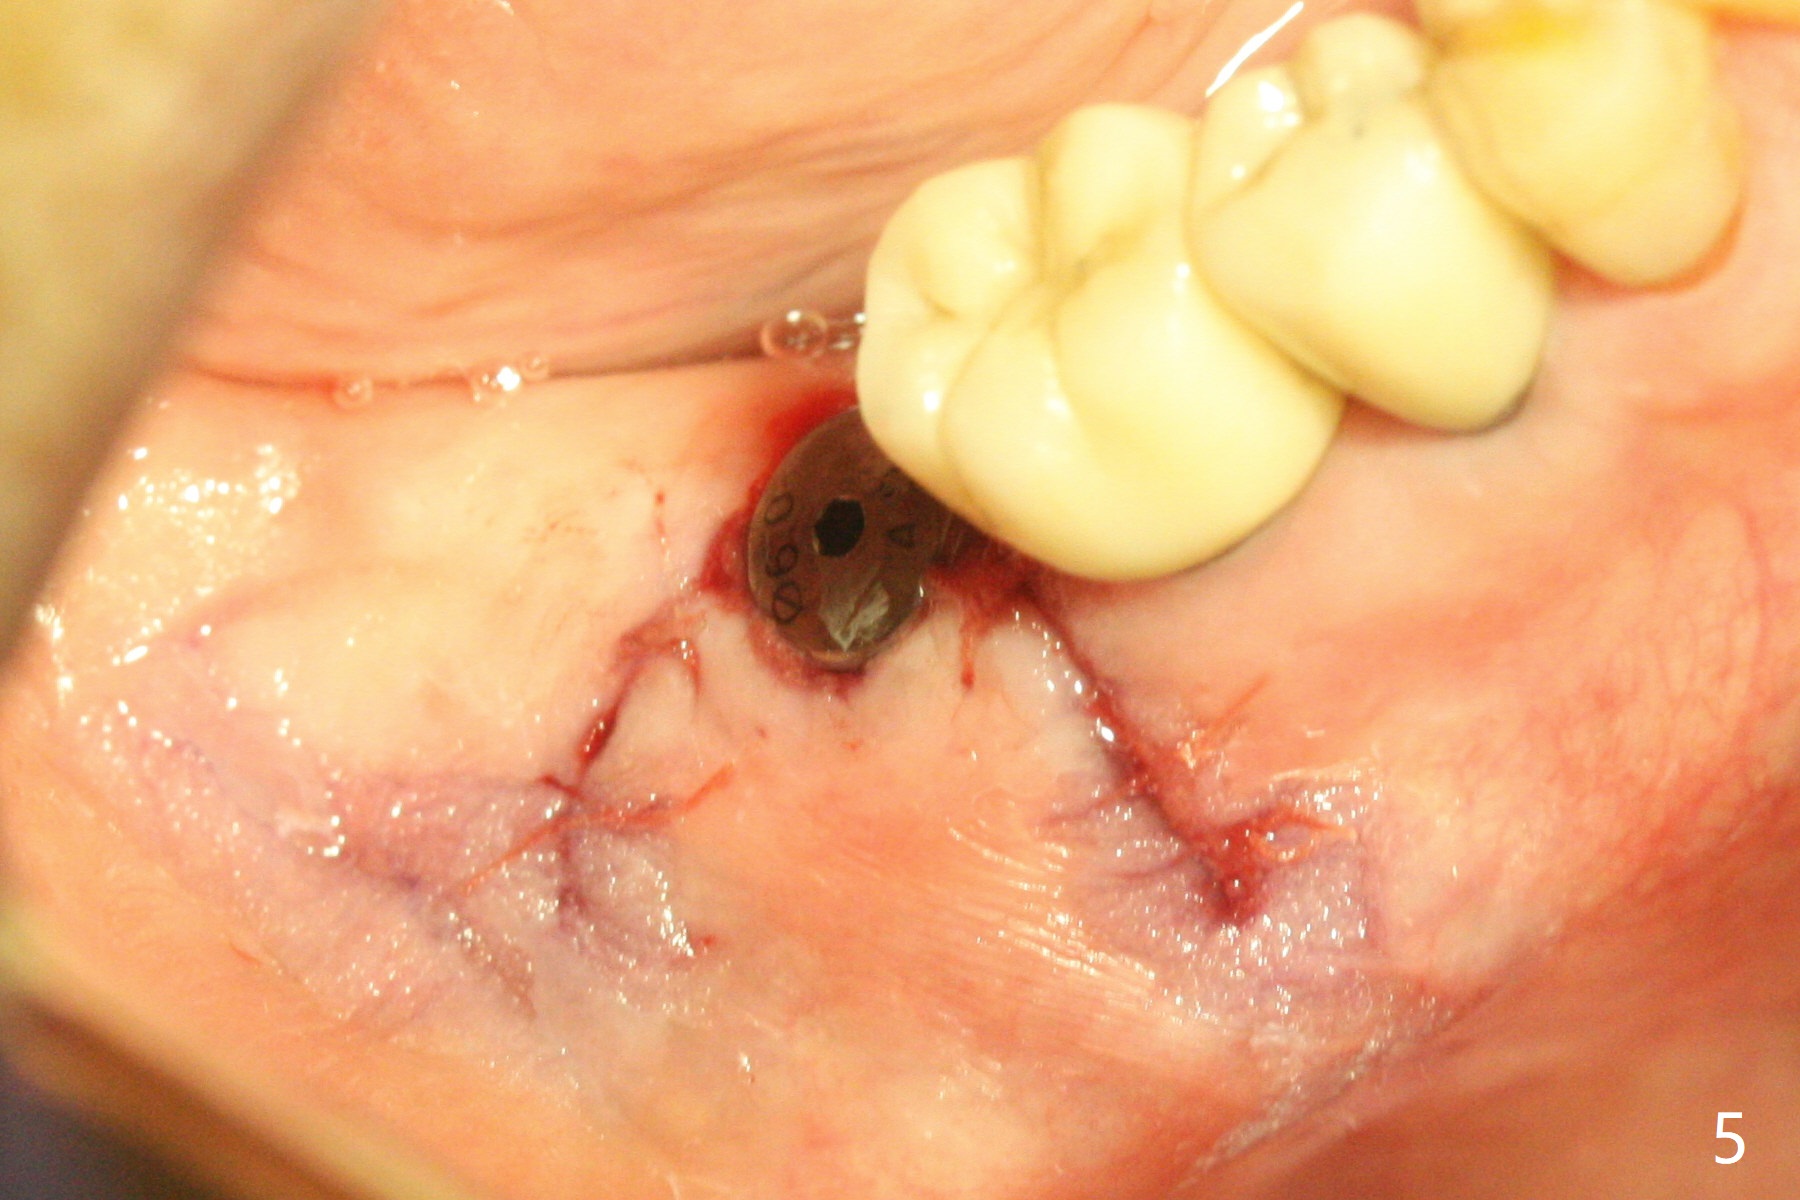

After 2.2x10 mm drill at #31 (Fig.1), bone expansion is conducted with 1.7/3.1 mm and 2.4/3.7 mm Expanders with guide (Fig.2) and 3.0/4.4 mm one without guide. Guided surgery resumes as planned to remove the lingual and apical bone. The buccal bone looks porous from the osteotomy opening. Mixture of autogenous and allograft is packed against the bone plate from the osteotomy before implant placement, but the 5x10 mm implant is unable to be seated completely. After removal of the bone graft from the osteotomy site and use of 4x11.5 mm drill for ~ 1 mm, the implant is seated with ~ 60 Ncm (Fig.3). With buccal incision, bone graft is placed over the distobuccal exposed implant thread (Fig.4 *) following placement of a 6x4 mm healing abutment. Oozing from the wound (thrombocytopenia) is controlled by Polysyn suture and perio glue (Fig.5). The mesial wound dehiscences 7 days postop when DO composite is placed at #28 (Fig.6). Two days later the patient returns because of hemorrhage in brushing. After placement of a taller healing abutment (6x7 mm) with triple antibiotic ointment (although the gingiva cuff is healthy), periodontal dressing is applied. Then the wound heals. The longer healing abutment remains seated (Fig.7 <) without interference from the crest (*) 4.5 months postop. A smaller cemented abutment (5.2x4(4) mm) is chosen with the same outcomes (well seated without gap (Fig.8 < between the implant and abutment), clearance from the crest (*)) 5 months postop. The final crown is cemented 6 months postop with distal access hole (Fig.9 black line), which may be related to design using normal 2nd molar tooth. In fact this patient has small teeth.